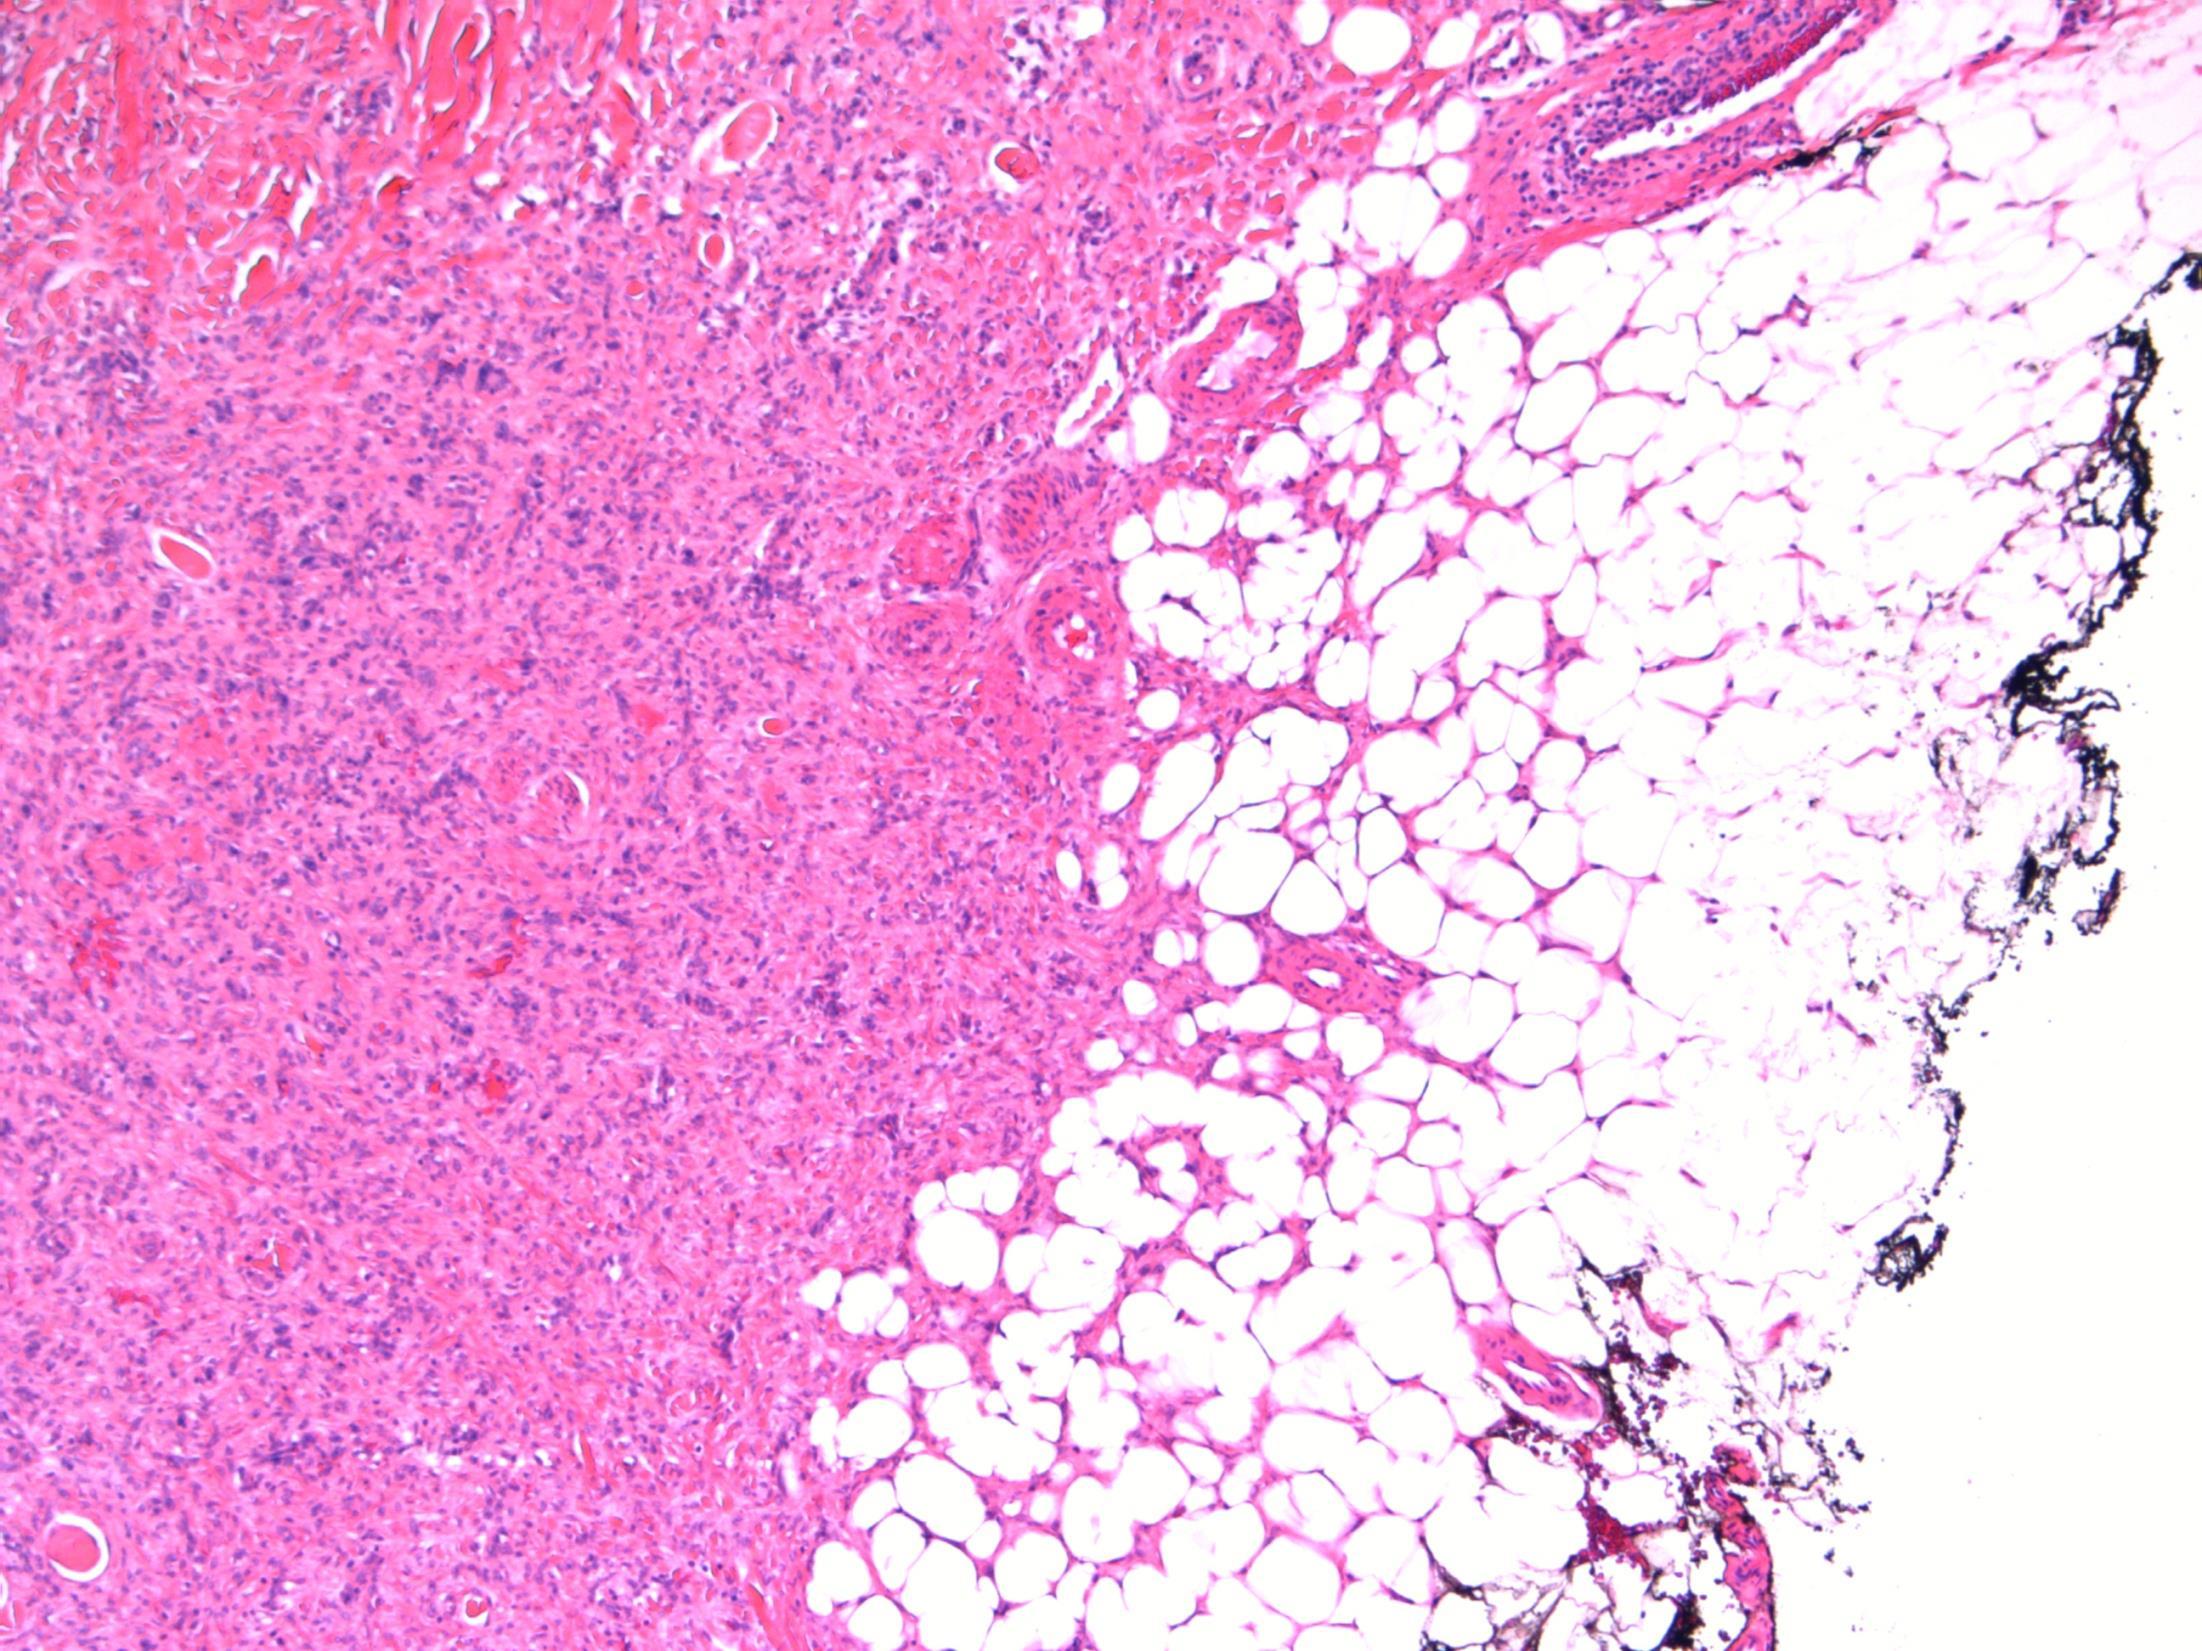

Liver Description: Liver containing well circumscribed spindle cell tumour with 3 components – smooth muscle cells (predominant), adipose tissue and blood vessels. Diagnosis: angiomyolipoma Differential Diagnosis: Leiomyoma (usually no prominent vascular or adipose component, negative for HMB45) GIST (CD117+) Mets of sarcoma / spindle cell carcinoma – more atypia Plan: IHC: SMA+, HMB45+, CD117-, AE1/3+ Correlate with clinical history ? Tuberous sclerosis etc Comments: • Liver is 2nd commonest site after kidney • Often detected incidentally, usually benign • May be sporadic but is associated with tuberous

and with TSC2 / PKD1 contiguous gene

(especially if

AML

sclerosis

syndrome

bilateral/multifocal).

3.5 Clinical features, associations 3.0 Differential diagnosis and use of IHC 2.5 Description with diagnosis or DD including AML 2.0 Differential diagnosis with mention of AML but favouring other diagnosis 1.5 Differential diagnosis with no mention of AML or a benign diagnosis 1.0 Malignant diagnosis Case 14